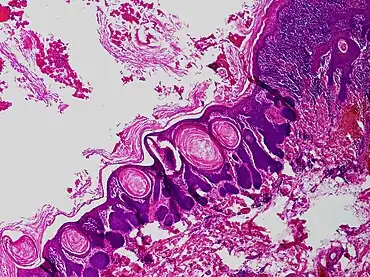

Trichofolliculoma

Trichofolliculoma is a non-cancerous, skin colored dome-shaped small or larger bump, with a central white tuft of hair typically on the face.[1] It may grow to around 7mm and sometimes there may be more than one.[1]

Histology